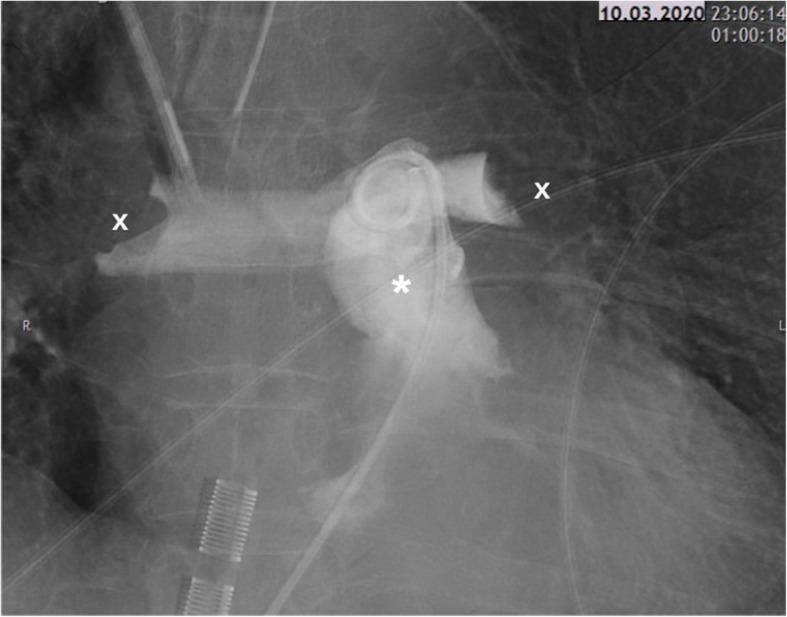

CASE PRESENTATION

We report two cases of high-risk perioperative PE. Both patients developed severe haemodynamic instability leading to cardiac arrest. After the implantation of a veno-arterial extracorporeal membrane oxygenation (ECMO), they were both successfully treated with USAT. Adequate improvement of right ventricular function was achieved; thus, ECMO could be successfully weaned after 3 and 4 days, respectively. Both patients showed favourable outcomes and could be discharged to rehabilitation.

病例报告

我们报告两例围手术期高危PE病例。两名患者均出现严重血流动力学不稳定,导致心脏骤停。在植入静脉-动脉体外膜肺氧合(ECMO)后,他们均成功接受了USAT治疗。右心室功能得到充分改善;因此,ECMO分别在3天和4天后成功撤机。两名患者均预后良好,可出院接受康复治疗。